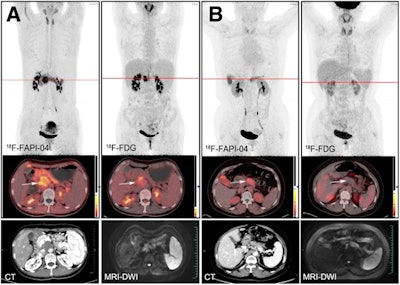

Typical PET (top), PET/CT (middle), and CT and MR (bottom) images of primary tumor obtained using both radiotracers in representative patients (A and B). Tumor is marked by arrows. DWI = diffusion-weighted imaging. Image courtesy of the Journal of Nuclear Medicine.

F-18 FAPI-04 PET/CT identified all patients with PDAC, while F-18 FDG-PET/CT missed one patient, according to the findings. F-18 FAPI-04 tracer uptake was higher than F-18 FDG in primary tumors (10.63 vs. 2.87, p < 0.0001), lymph node metastasis (2.9 vs. 1.43, p < 0.0001), and distant metastases (liver, 6.11 vs. 3.1, p = 0.002; peritoneal, 4.7 vs. 2.08, p = 0.015).